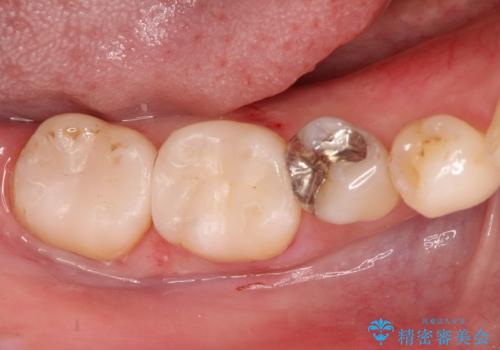

保険診療のCRインレーをセラミックインレーでやり直し

- 定期検診にて他院で治療された保険適用CRインレー部分(大臼歯2本)にむし歯を認めたため、セラミックインレーにて修復を行いました。

e-max プレスインレーにて修復治療を行っているため適合性及び審美性の高い治療を行うことができます